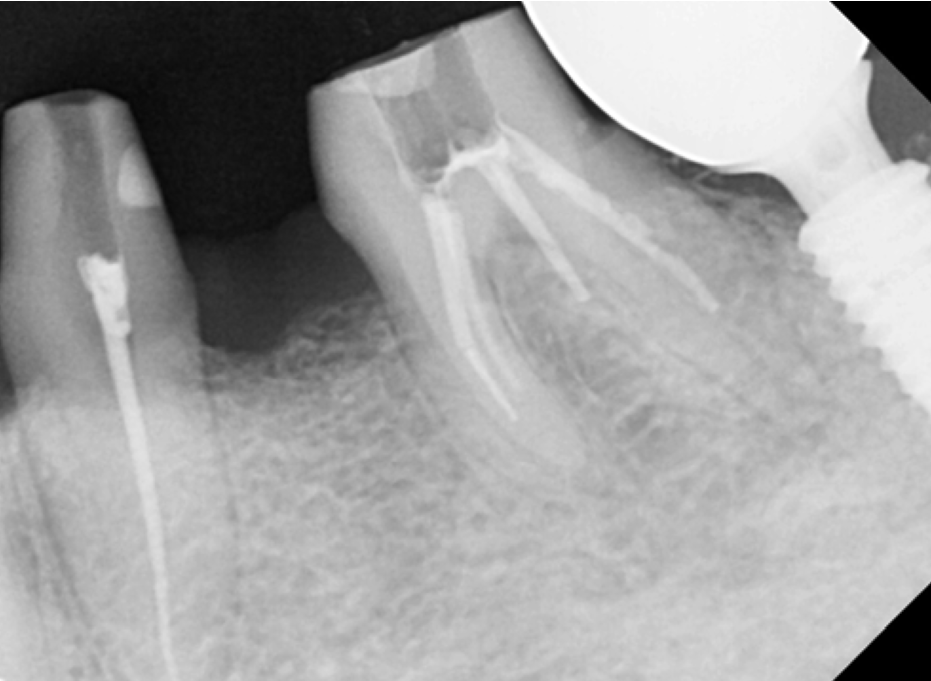

확대해서 보는 치근단 엑스레이 보시면,

하얗게 뿌리부분에 신경치료 재료가 잘 들어가

잘 마무리 된 것을 볼 수 있습니다.